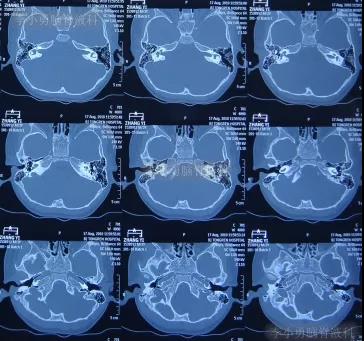

患儿先天性聋哑,在3岁时即在2010年8月17日,于第1家北京某著名三甲医院进行了颅底耳蜗周结构的CT检查(图-1)。

图-1:2010年8月17日耳蜗周颅底CT